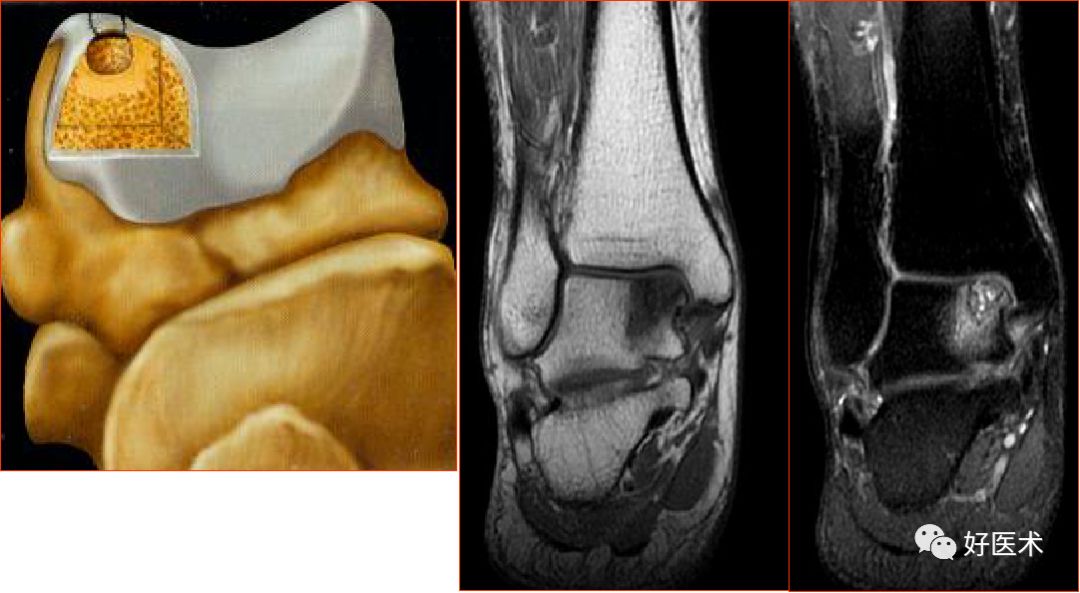

三、骨软骨病变

距骨骨软骨损伤,好发于前外侧、后内侧,尤其是后内侧,与内外翻损伤相关。

距骨骨软骨损伤分级